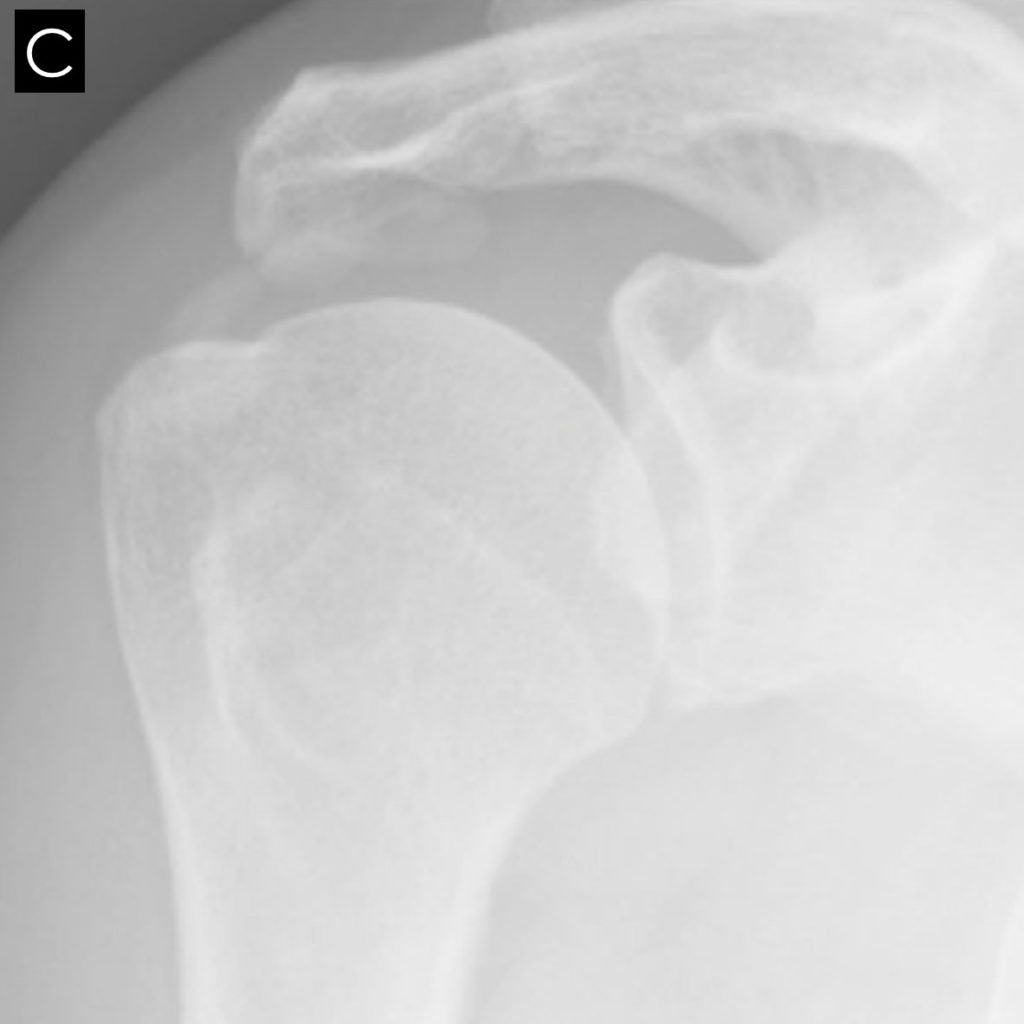

From cambridgeshoulder.co.uk

Fig 27. XRay Ca deposit Cambridge Shoulder What Do Calcium Deposits Look Like On X Ray Calcifications appear as white areas of varying size and shape. This test measures the level of calcium in your blood. When your doctor tells you that you have calcified arteries, it is usually after you have had a coronary calcification scan. Microcalcifications are tiny calcium deposits that may be seen in thyroid nodules, some of which could be cancerous. Recognising. What Do Calcium Deposits Look Like On X Ray.